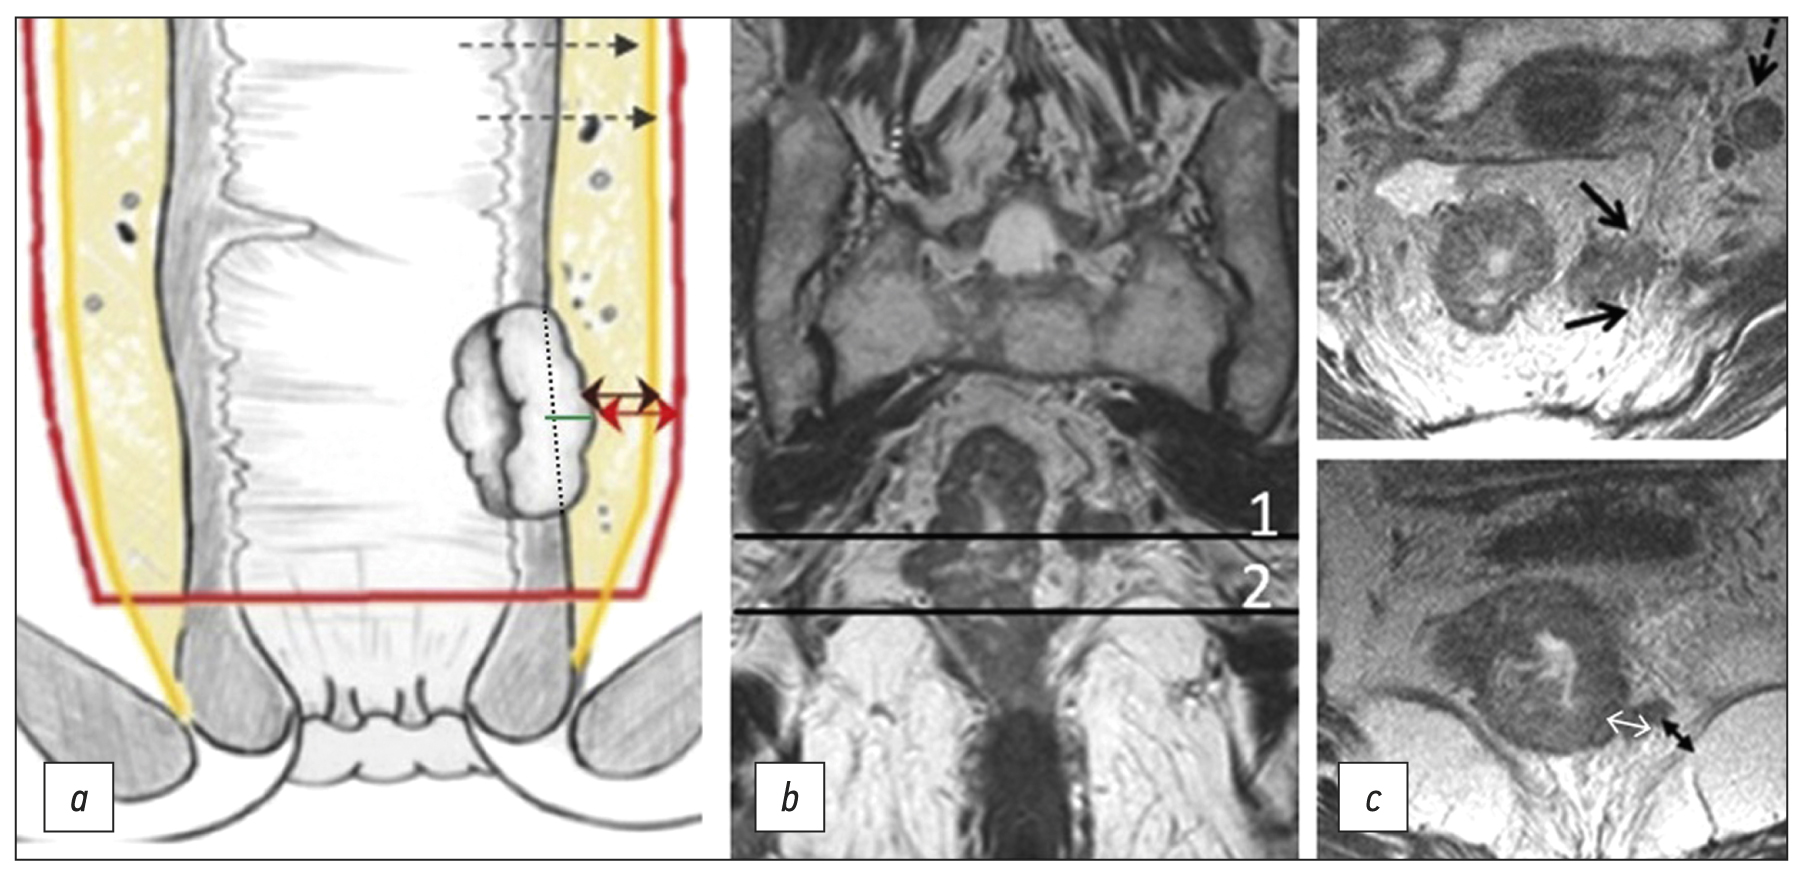

The depth of extramural invasion is the maximum distance from the outer edge of the muscular layer of the wall at the base of the extramural component of the primary tumor to its outer edge, as observed on high-resolution T2-WI oriented perpendicular to the intestinal wall at the level of the tumor (Fig. 2). The depth of extramural invasion is used to determine the substage of T3 tumors.

Fig. 2. Circular border (edge) of rectal resection during total mesorectumectomy. (a) Diagram showing extramural growth of the tumor (green line); mesorectal fascia (yellow line); circular border (edge) of resection (red line); distance from the tumor to the mesorectal fascia (double black arrow); distance from the tumor to the circular border (edge) of resection (double red arrow). (b) T2-weighted images in the coronal plane of the tumor of the lower ampullary part of the rectum with extramural vascular invasion and deposit at the level of axial T2-weighted images. (c) Upper axial section corresponds to the level of the deposit involving the mesorectal fascia (black arrows), extramesorectal lymph node (dotted arrow). The lower axial section corresponds to the level of extramural vascular invasion. The depth of extramural invasion (a double white arrow). The distance from the tumor to the elevator muscle of anus (a double black arrow).

Circumferential resection margin (CRM) is a surgery and pathology term defined as the surface of surgical excision of the non-peritoneal part of the rectum, which should pass along the mesorectal fascia when performing a total mesorectumectomy.

The status of CRM is determined by histological examination of the surgically removed rectum specimens. It can be predicted based on MRI by the shortest distance between the extramural component of the tumor/deposit/affected lymph node and the mesorectal fascia. Involvement of the CRM is indicated as CRM(+) if this distance is ≤1 mm. For low-lying rectal cancer, the shortest distance is determined to the elevator muscle of anus. The distance from enlarged lymph nodes without signs of extracapsular spread (with smooth contours) is not considered and should be regarded as CRM(−) [13].

Extramural vascular/venous invasion in histological examination represents intravascular growth of the tumor beyond the rectal wall, serving as a predictor of poor prognosis, lymphatic and distant metastases, and tumor recurrence [14–17]. On T2-WI, extramural vascular/venous invasion is characterized by the spread of a tumor signal into the vascular structures of the mesorectal tissue [6, 18, 19], which can be combined with the increased diameter of the affected vessel or with the tumor extending beyond its walls with the formation of a node, beaded, or worm-like structure. It is important to note that the MRI assessment of extramural venous invasion in vessels less than 3 mm in diameter is unreliable. When determining the category “T” (T3 and T4 tumors) in cases of fusion of the primary tumor and an extramural venous invasion lesion, their total size should be considered.